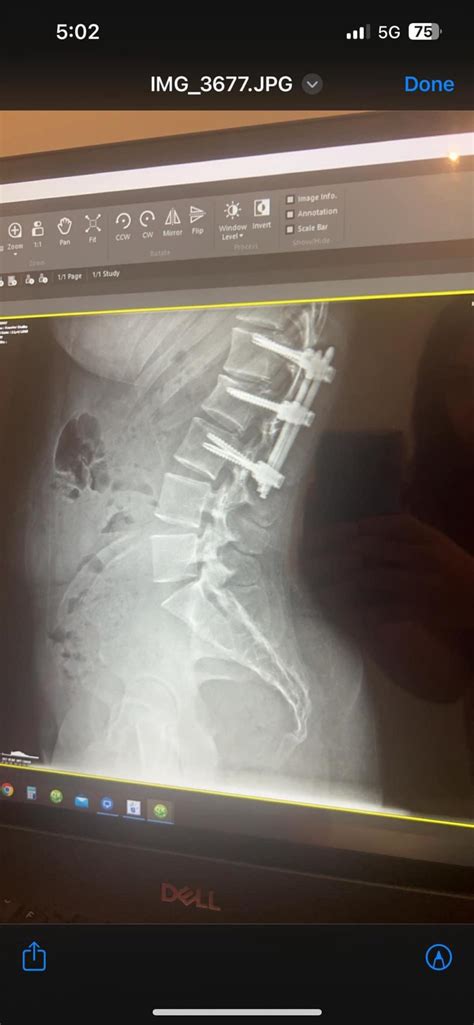

Georgia Butler Blog